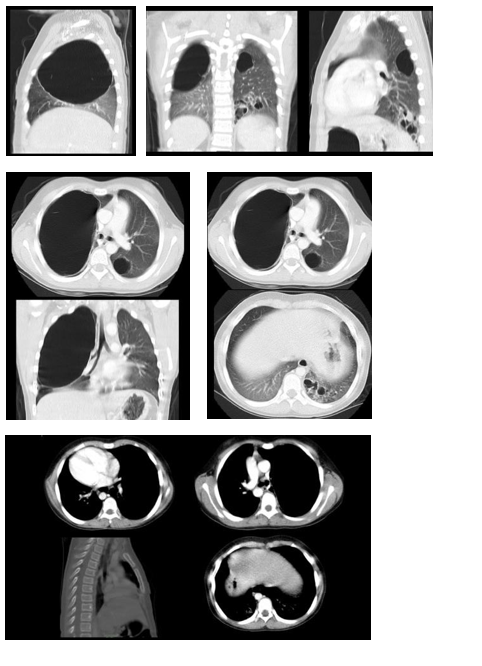

The soft tissue ultrasound of the scalp reported three collections with a total volume of 26 cc, and the gluteal ultrasound reported a small collection of 1cc. The chest x-ray showed an image of a radiolucent cyst in the apex of the right lung and middle lobe atelectasis. (Figure 1) A chest CT scan showed cystic lesions involving the right upper lobe and the segments of the left lobe, with bronchiectasis. (Figure 2)

Figure 1 Chest X-Ray.

Figure 2 CT Scan Approximate volume of 636 cc.